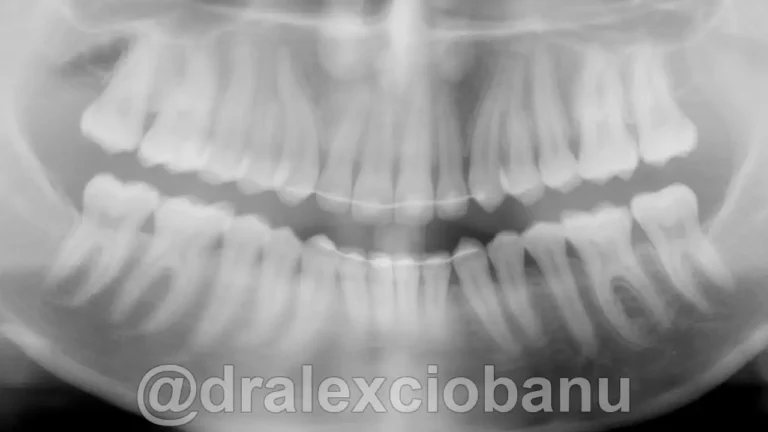

I brackets linguali possono allineare sia le corone che le radici dei denti, in modo che siano perfettamente posizionati l’uno accanto all’altro in posizione corretta. È spesso difficile ottenere questo posizionamento utilizzando gli allineatori rimovibili, specialmente quando si tratta di correggere le rotazioni dei canini. I brackets linguali fissi possono posizionare perfettamente i canini e i denti anteriori nella posizione corretta, come mostrato nella radiografia orto panoramica al termine della terapia.

Abbiamo corretto il morso ed ottenuto il perfetto allineamento dei denti.

Tempo totale di trattamento: 10 mesi.